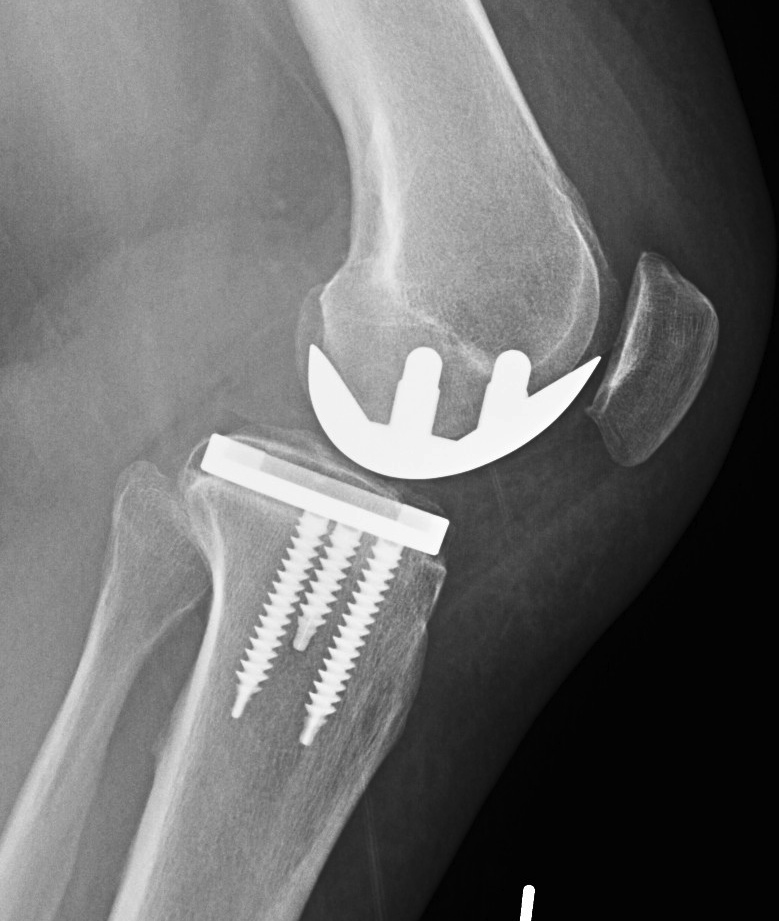

Patient 1

Patient 2